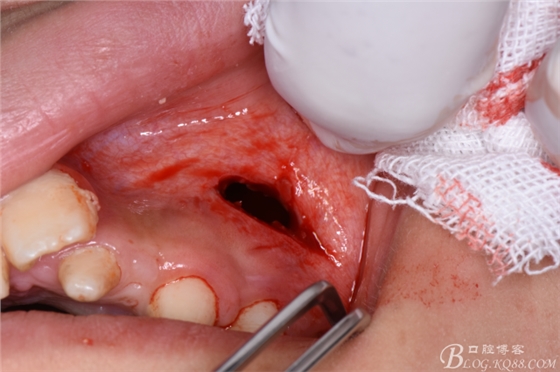

圖7.在24根尖區(qū)的前庭溝黏膜處垂直進(jìn)刀

圖8.做凸面朝向齦方的弧形切口

圖9.翻瓣、暴露出骨面

圖10.去骨